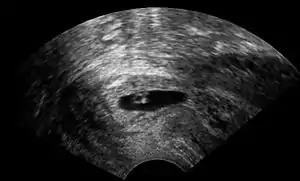

| Vaginal ultrasonography of a cervical pregnancy at a gestational age of five weeks. See image below for details of the visible structures.[1] | |

The diagnosis is made in asymptomatic pregnant women either by inspection seeing a bluish discolored cervix or, more commonly, by obstetric ultrasonography. A typical non-specific symptom is vaginal bleeding during pregnancy. Ultrasound will show the location of the gestational sac in the cervix, while the uterine cavity is "empty". Cervical pregnancy can be confused with a miscarriage when pregnancy tissue is passing through the cervix.